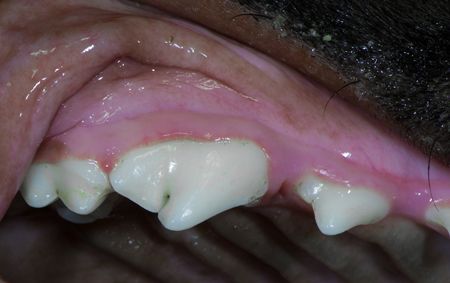

And one week later, the gingivitis was on the way to complete resolution.

A discussion with the client about embracing home oral care including daily plaque control will help prevent further gingival problems from arising in Rylee. For more on identifying periodontal disease, click here.